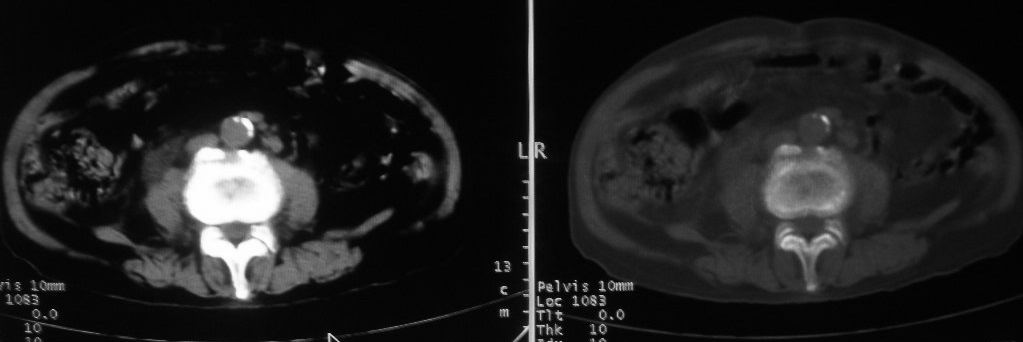

以下是引用深泽交通医院在2008-10-3 15:33:00的发言:[br]前列腺实性增大伴分叶状,与包膜间隙境界不清;椎体松质区间结节样密度影,考虑:前列腺癌,并椎体成骨性转移

以下是引用zjzjr在2008-10-3 12:59:00的发言:[br]前列腺癌伴左髂骨\\腰椎转移可能性大.

以下是引用卜一在2008-10-3 13:40:00的发言:[br]前列腺癌!左髂骨\\腰椎转移?建议行全身骨扫描!